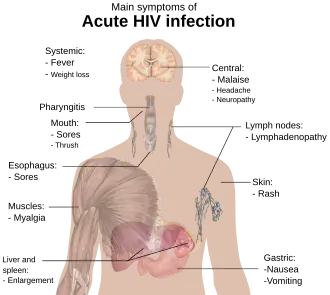

Due to media images of the effects of AIDS, many people believe that individuals infected with HIV always appear a certain way, or at least appear different from an uninfected, healthy person. In fact, disease progression can occur over a long period of time before the onset of symptoms, and as such, HIV infections cannot be detected based on appearance.[26]

HIV cannot be transmitted through oral sex